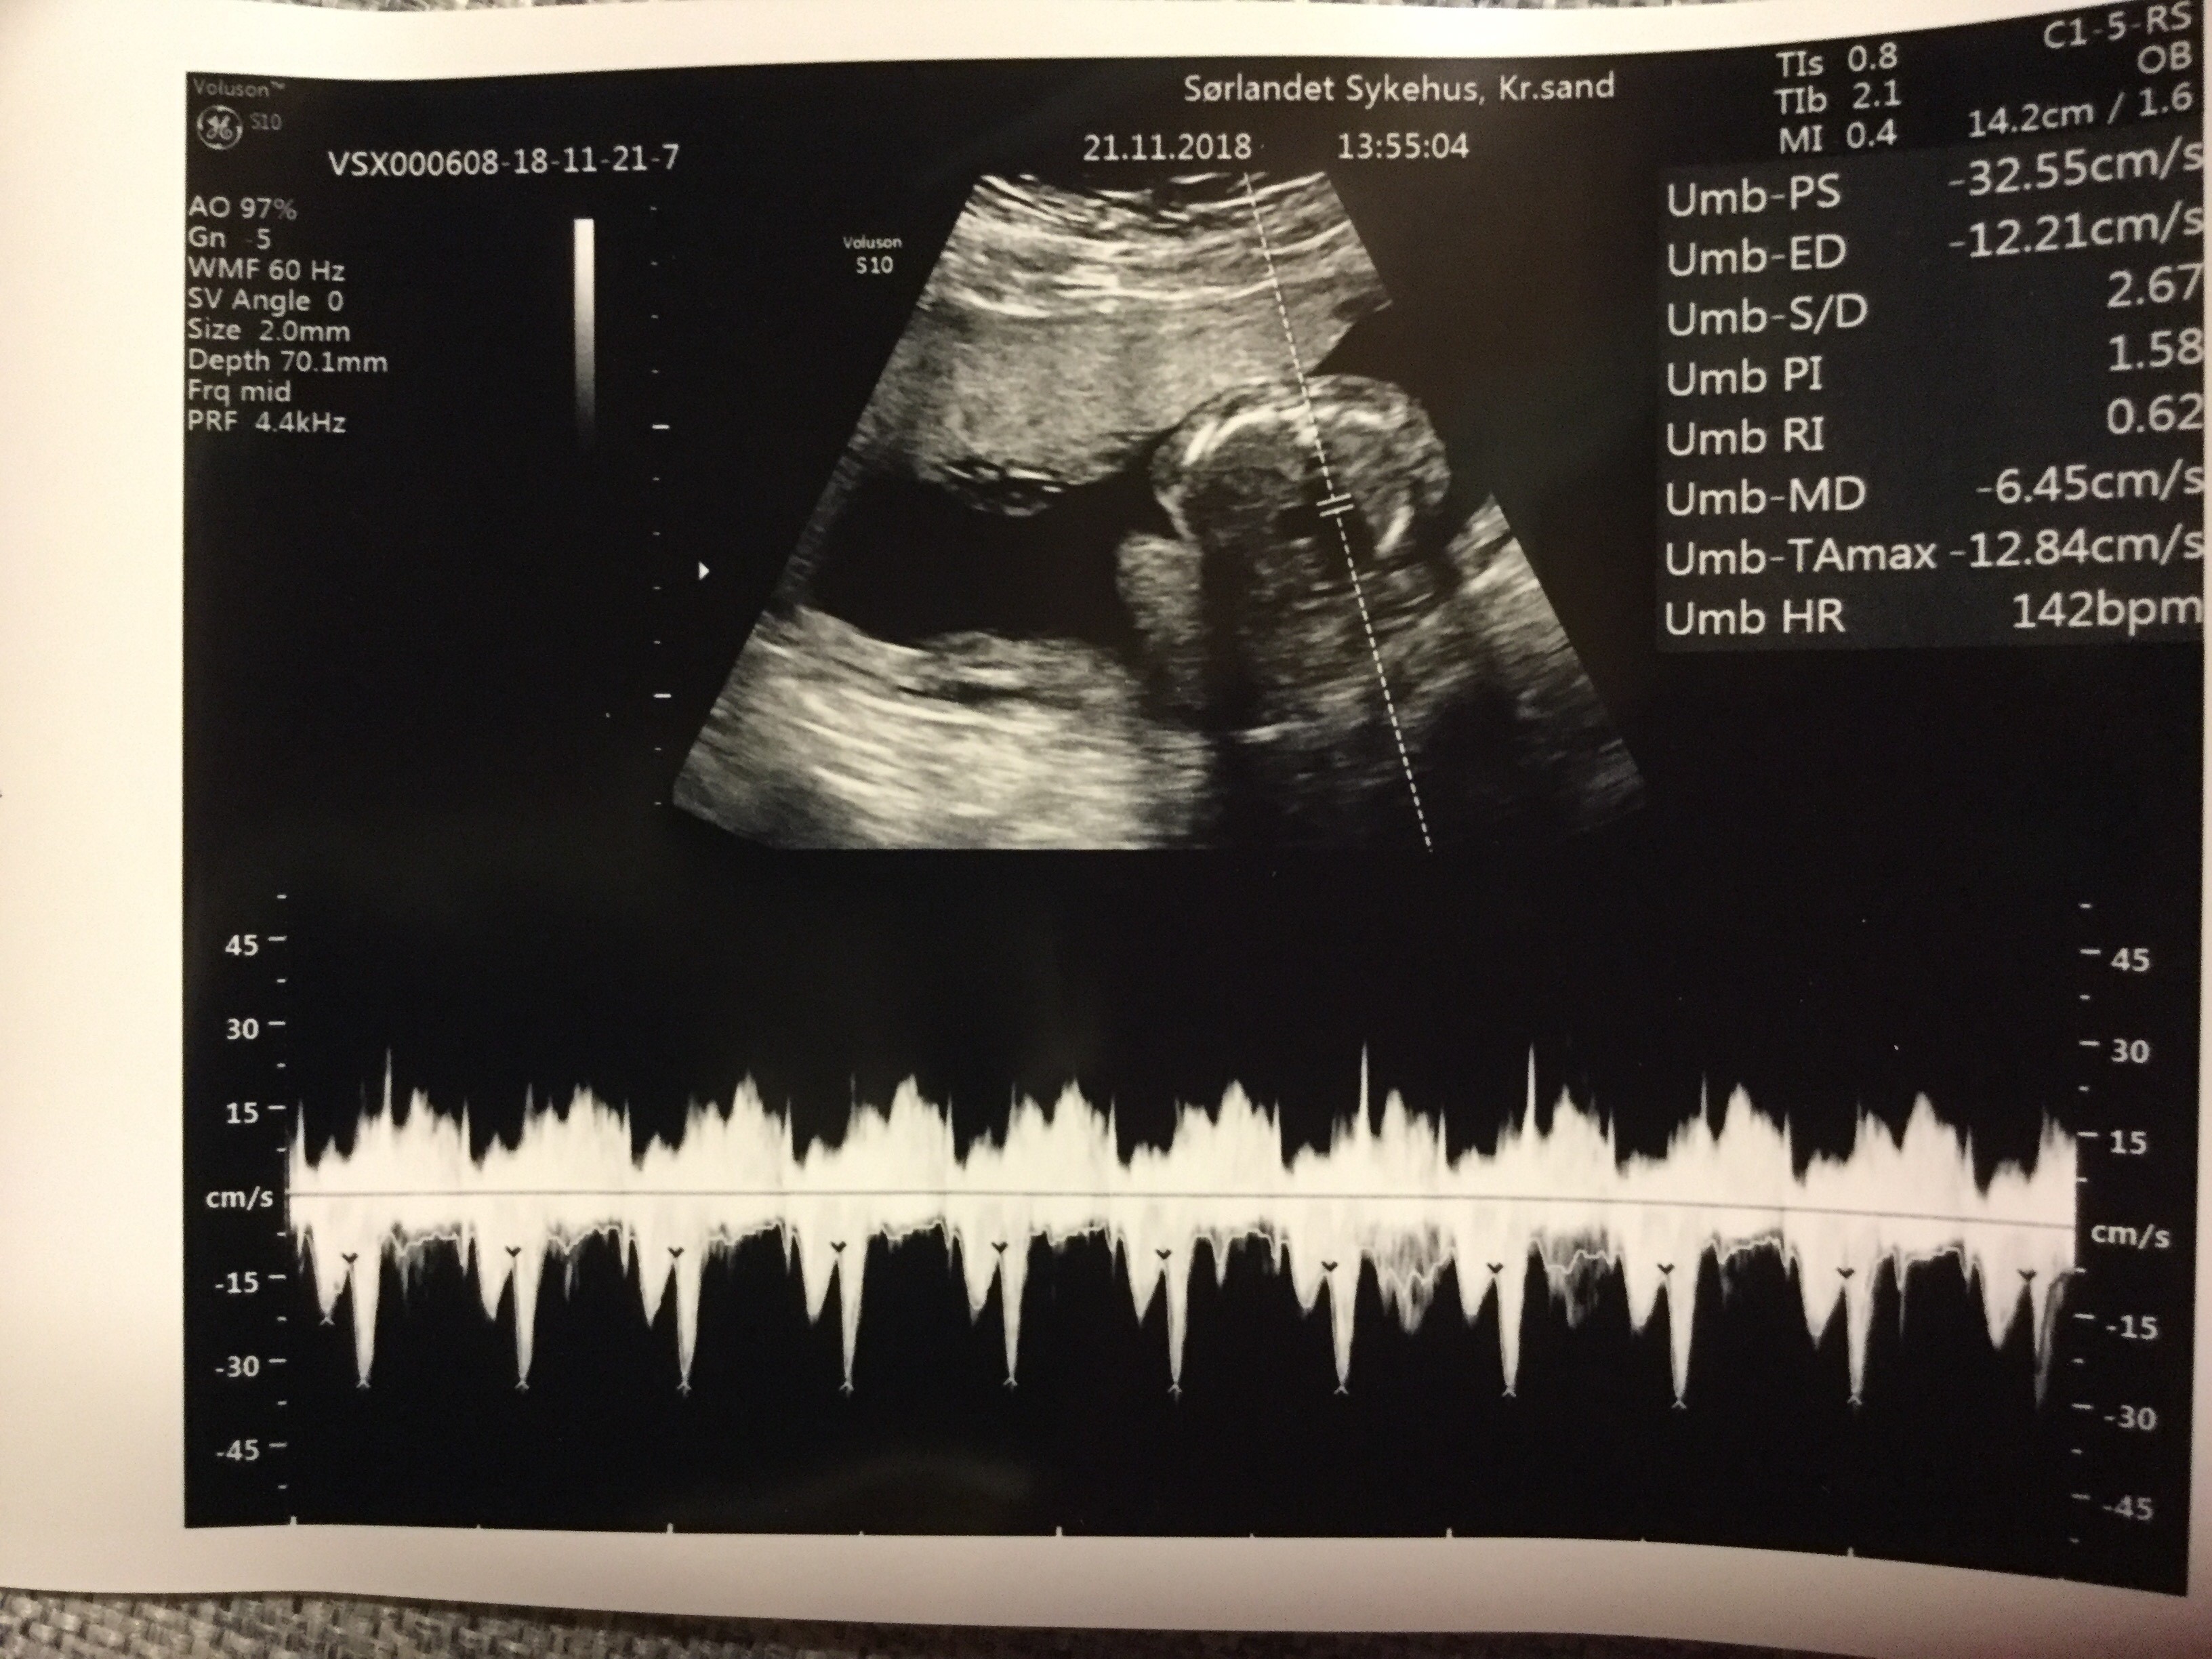

inCollage_20181121_152754519.jpg

• inCollage_20181121_152754519.jpg

423,8 KB · Wyświetleń: 4 296

19+0 (wg usg i tego się teraz trzymamy!) wg OM 20+0

Waga : prawie 250 g i prawie 22 cm :biggrin2:

Tętno : 144(wczoraj), 150 (dzisiaj) :biggrin2:

Płeć : 100% chłopak :-) :)

Imię : Gabriel Mirosław :biggrin2:

Nosek - widoczny i śliczniutki (na prenatalnych podobno kośc nosowa była „nie do oceny”!)

Łożysko : na przedniej ścianie

Szyjka : 5 cm

Wszystkie narządy rozwijają się prawidłowo :-) :)

Termin porodu wg usg 20.04.2019 (jednak ze względu na cukrzycę typu2 nastąpi on 2 tygodnie wcześniej,ale konkretną datę poznam w późniejszym terminie) :-) :)